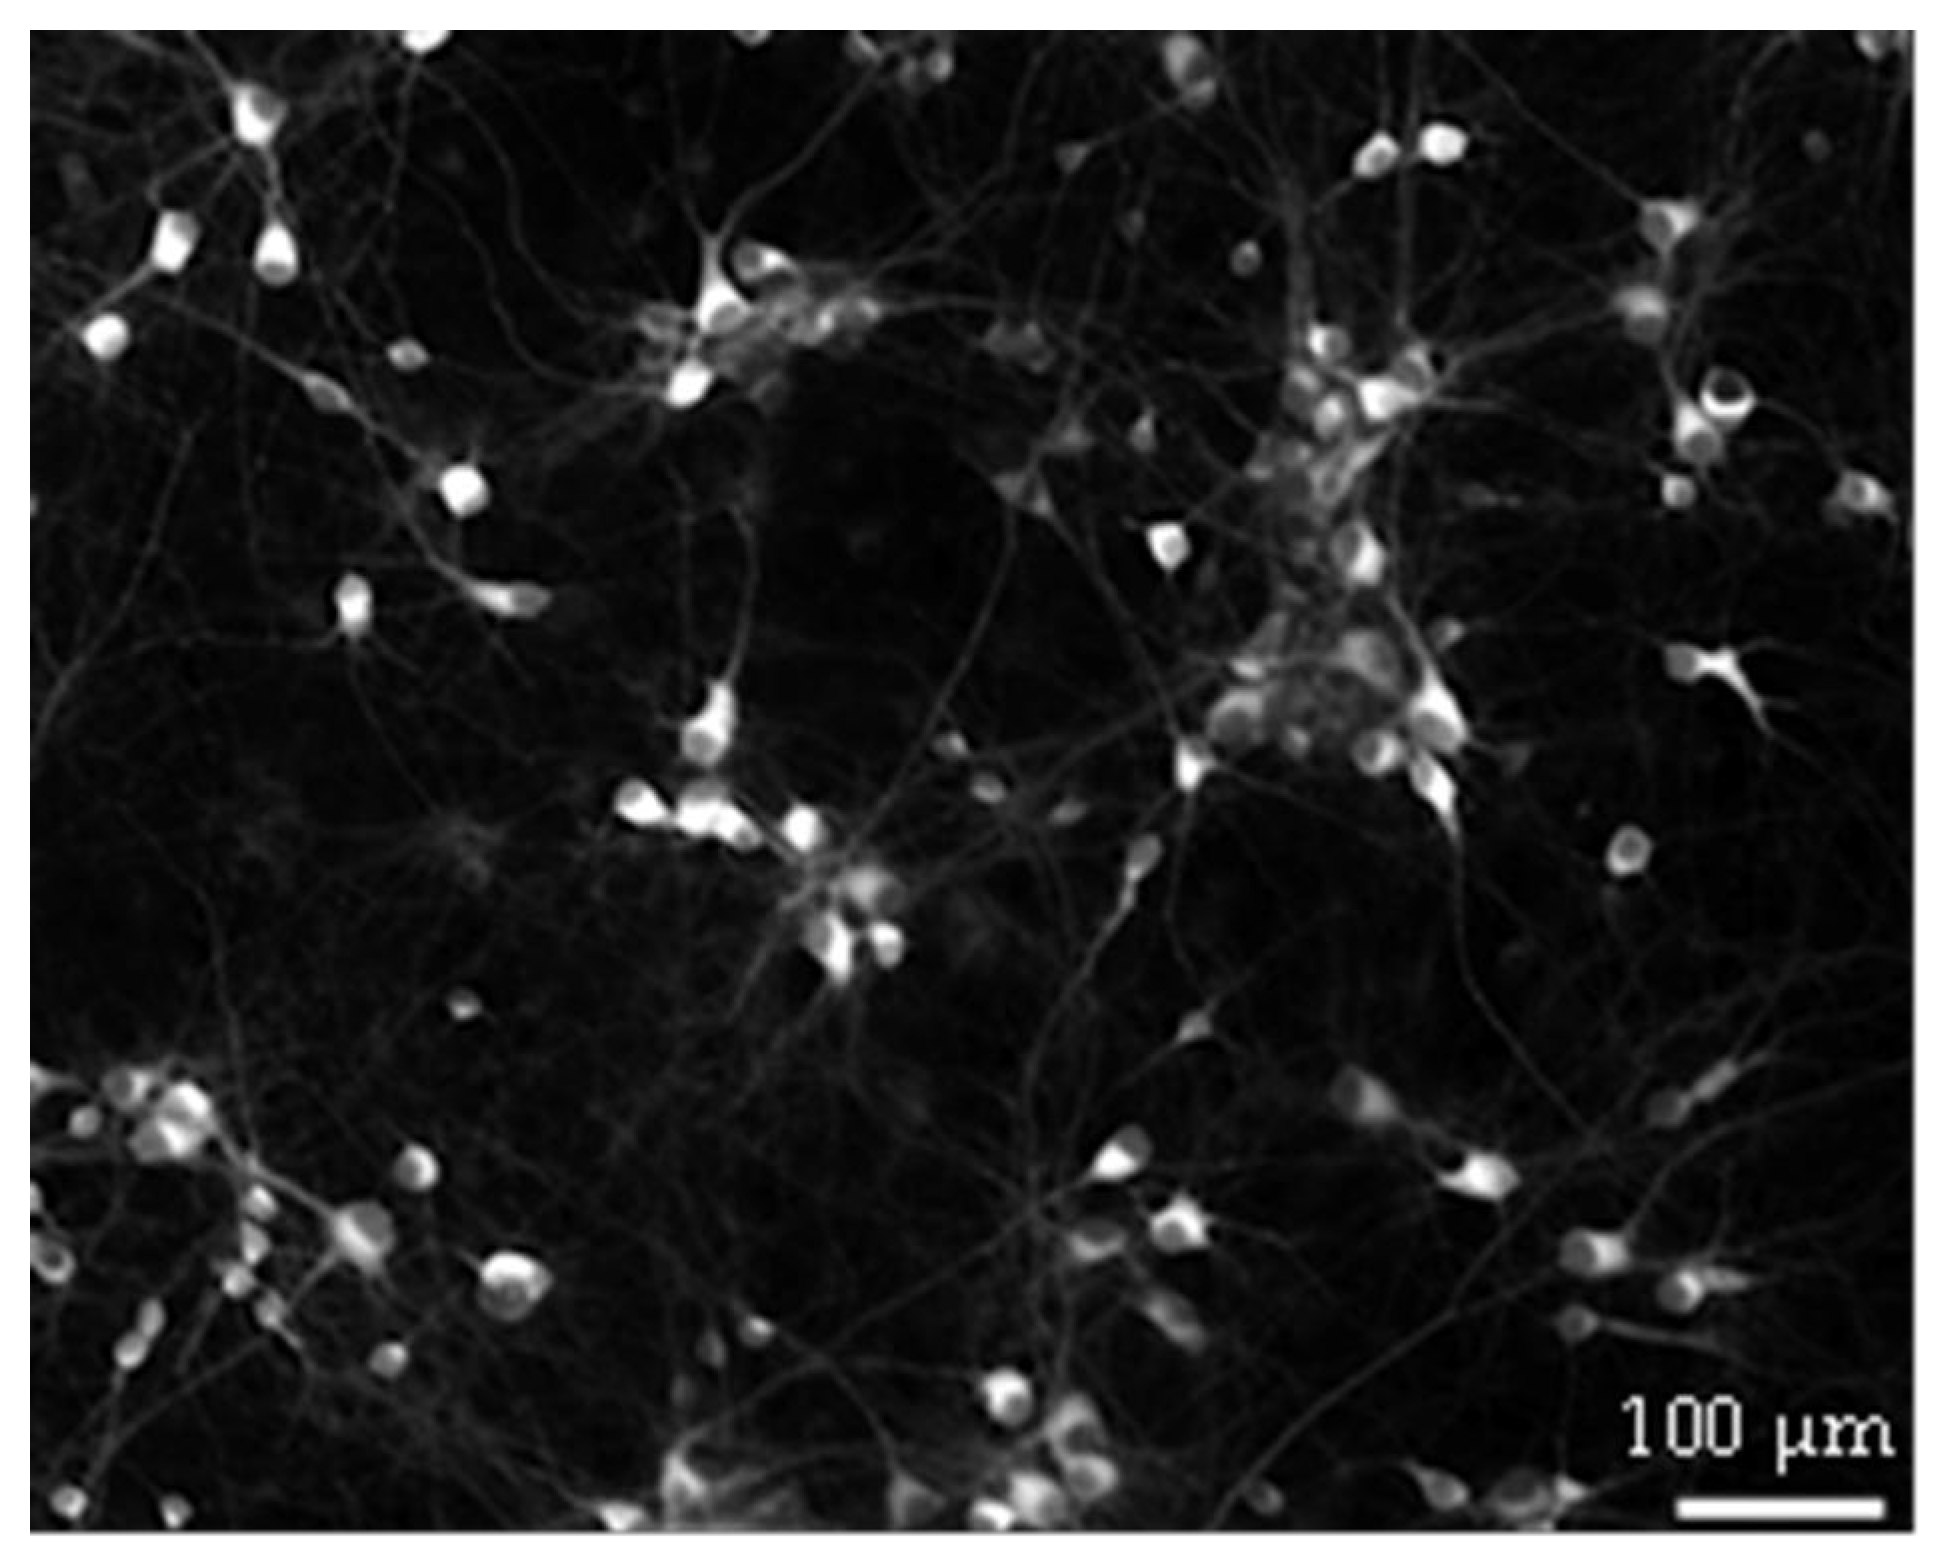

Further research is needed to explain why GAA causes a decrease in the above-mentioned parameters upon its acute addition at the 10 µM concentration and of all the parameters at the 100 µ concentration. One possibility is that GAA at these concentrations may have some hypothetical still unknown toxic effect on neurons. However, it is hard to provide an answer to this question with the current configuration. To generate a sustained spontaneous activity, neurons must be plated over the MEA surface at high density (about 1200–1500 cells/mm2, see Figure 7). At this density, it is impossible to solve the neuronal morphology by using both the differential interference contrast microscopy and the immunofluorescence technique; thus, it becomes impossible to appreciate possible variations/alterations in the morphology at the single neuron level.

Figure 7.

Example of hippocampal neurons plated on Micro-Electrode Array (MEA) at DIV 18. Neurons established a dense connectivity which made it hard to solve their morphology.